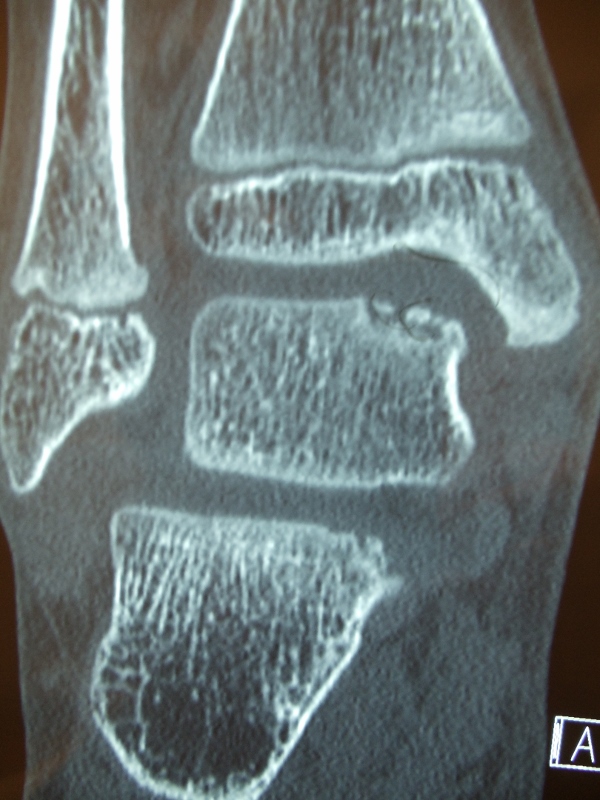

Series of Pics of Microfracture of large OCD of the Talar Dome

Osteochondral Autograft Transfer System (O.A.T.S.)